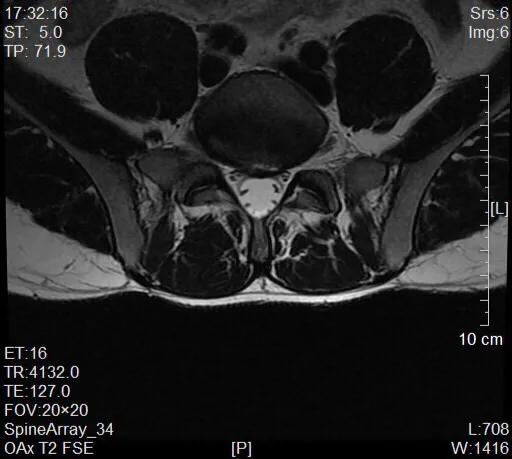

16日预期的复诊,核磁共振检查结果显示如下

我与患者解释一下为什么,和我之前矫正骨盆意外地治好我堂兄痔疮出血的情况。我初步诊断:骨盆旋移综合征,予相关体格检查后与美式整脊手法治疗患者髂骨前后倾和旋转的问题,并相应治疗寰椎。患者体态和肛门、骶部疼痛的症状随之有所缓解。因我19日要到广州学习,嘱患者到中医科继续理疗,可以28日找我复诊。